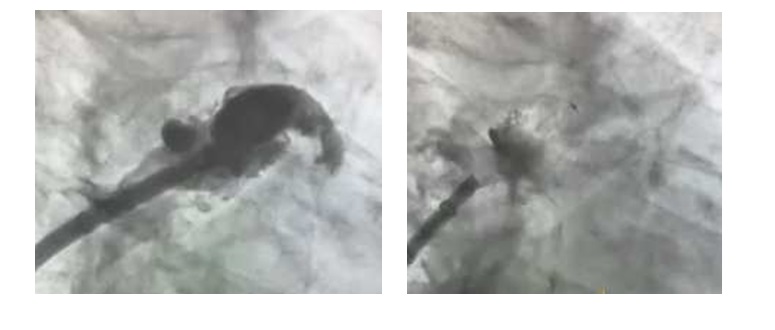

Ακτινοσκοπικές λήψεις από την σκιαγράφηση του ωτίου του αριστερού κόλπου και από την τοποθέτηση της συσκευής σύγκλεισης του ωτίου.